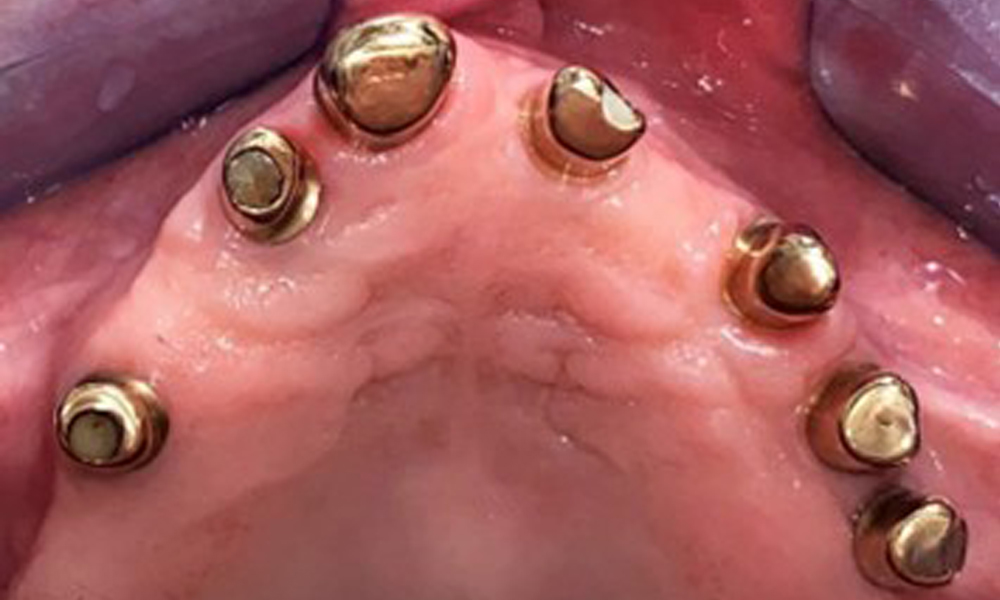

На пациентката е поставена комбинирана подвижна горночелюстна телескопична протеза преди повече от 25 години (фиг. 1, фиг. 2, фиг. 3) и тя е много доволна от протезите си. Пациентката има адекватна фиксирана протеза за долната челюст (фиг. 4).

Денталните открития са следните: Комбинирани снемаеми протези на импланти и телескопични протези, поддържани от зъби, на импланти 15, 13, 21, 23, 24, 25 и зъб 11 (фиг. 1, фиг. 2, фиг. 3). Пациентът е снабден с фиксирана долночелюстна протеза. Над зъби 37-34 и 45-47 бяха налични адекватни мостове (фиг. 4), краищата на коронките бяха интактни и нямаше активен кариес. Върху зъб 43 имаше композитна пломба с маргинална празнина. Имаше рецесия на долната гингива, която разкриваше от 1 до 3 mm от кореновата повърхност. Това се отнася и за 11.